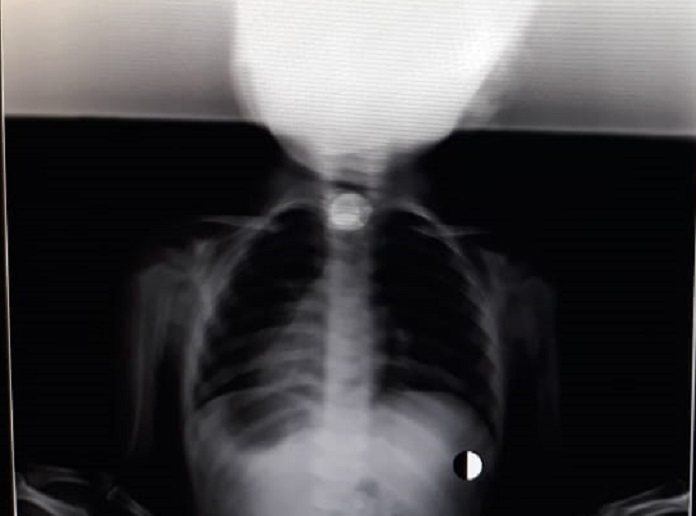

Ребенок поступил в приемный покой центральной районной больницы Бейнеу с жалобами на кашель и затрудненное дыхание. Об этом сообщили в управлении здравоохранения Мангистауской области.

Инцидент произошел 18 марта. В приемный покой центральной районной больницы Бейнеу поступила двухлетняя девочка с инородным телом в дыхательных путях, которое вызвало затрудненное дыхание и кашель.

- Не дожидаясь отправки ребенка в областную детскую больницу, врачи приняли решение своими силами вытащить инородный предмет из дыхательных путей, используя «Катетер Фолея». По словам директора больницы, данную методику он изучил из опыта испанских врачей, которые идентичным образом вытащили монету из дыхательных путей другого ребенка. На данный момент ребенок чувствует себя хорошо, - сообщили в управлении здравоохранения Мангистауской области.